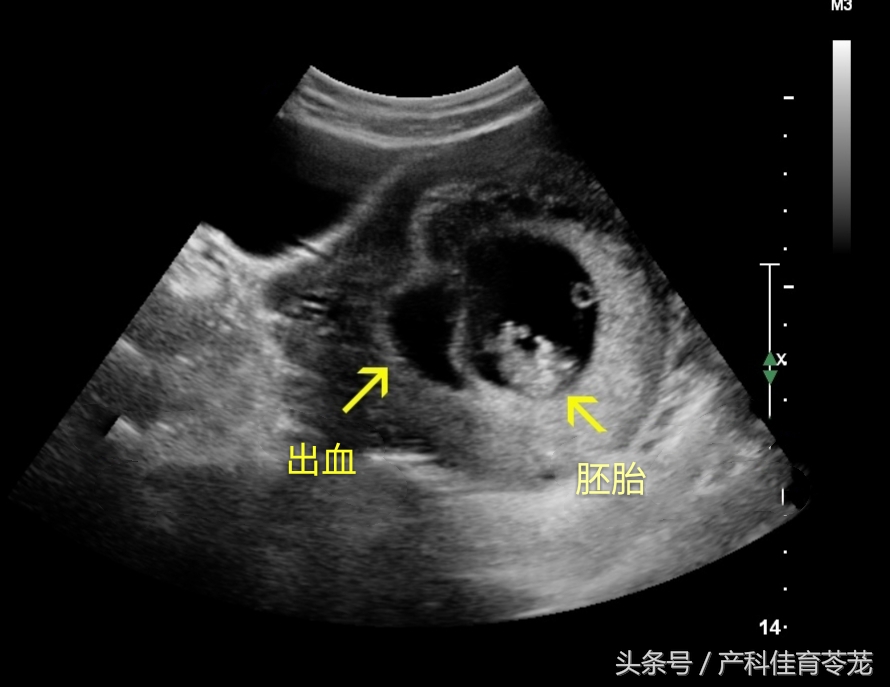

当B超看到这样的图像:

B超医生会在您的报告单上这样写:

宫腔内液性暗区,请结合临床;

孕囊旁出血/胎膜后积血/绒毛膜下出血......

就是在绒毛膜与孕囊之间或者子宫与胎盘之间有血液聚集,通俗点说就是出血和胚胎之间还隔着一层膜或者胎盘,发生原因不详。